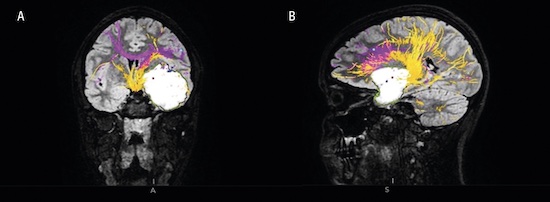

Essentiell tremor är en folksjukdom som drabbar 5 procent av populationen över 65 års ålder, och farmakologisk behandling hjälper endast omkring hälften av dem. Djup hjärnstimulering är hos denna patientgrupp vanligen mycket effektiv, och man kan förvänta sig att kontralateral arm- och handtremor reduceras med omkring 80‒90 procent (Figur 2) [6].

Figur 2. T2-viktad axial MRT-sekvens, som visar en elektrod för djup hjärnstimulering belägen i subtalamisk vitsubstans hos en patient med essentiell tremor.